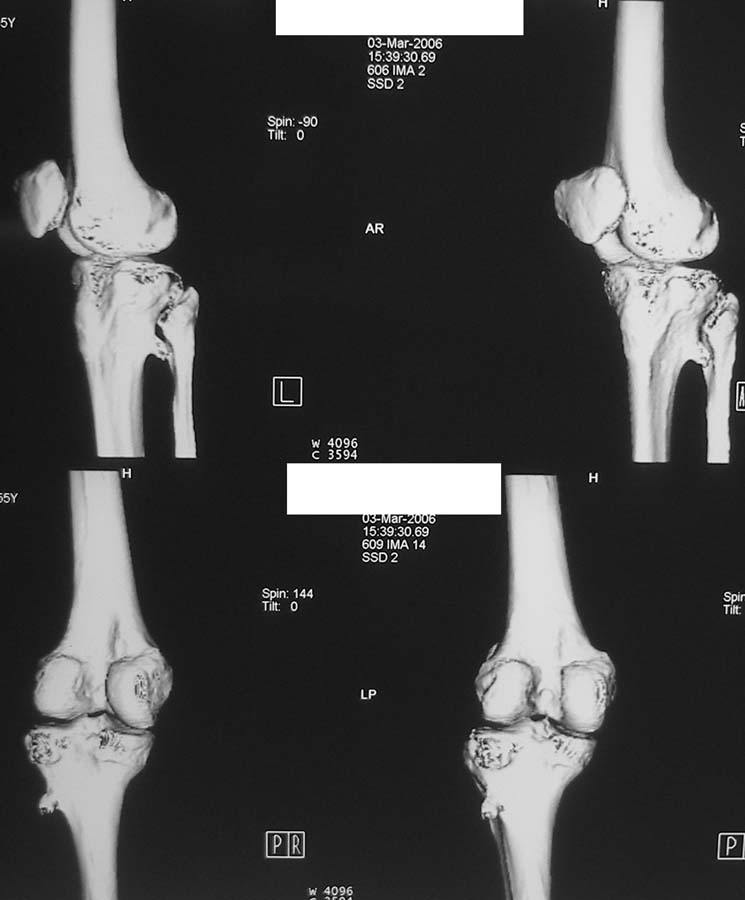

Женщина, 55 лет. С 2002 года - гонартроз. В настоящее время - боли в коленном суставе, стартовые боли, иногда в ночное время (проходит <от перемены положения ноги>).

Принимает НПВС, артрон-комплекс, внутрисуставно гиалган. Ревмопробы отрицательные. На рентгенограмме отметили сужение шейки малоберцовой кости, на спиральной КТ - экзостоз? Ваше мнение о целесообразности операции (велика вероятность повреждения нервов), предварительной биопсии?Спасибо! С уважением, А.В.Владзимирский Донецкий НИИ травматологии и ортопедии Донецк, Украина

Если боли связаны с гонартрозом, то показано тотальное эндопротезирование коленного сустава. Тип эндопротеза - мыщелковый, с сохранением задней крестовидной связки, сейчас таких моделей много (LCS, Balansis, Genesis, Scorpio, КЭКС-01 и другие, всё зависит с какими фирмами Вы работаете). Вопрос об удалении остеохондромы спорный, с одной стороны маловероятно ожидать у женщины 55 лет быстрого перерождения во вторичную хондросаркому при такой рентгенологической картине. Можно спротезировать коленный сустав и проводить рентгенконтроль каждые 6-12 мес. С другой стороны, если спротезировать и оставить остеохондрому, а она начнёт интенсивно рости, то её последующее радикальное удаление может ослабить тибиальный компонент эндопротеза. Проявляя онкологическую настороженность, остеохондрому лучше удалить первым этапом, до эндопротезирования с интервалом между операциями 6 мес. Производить биопсию в данном случае однозначно не целесообразно, так как при перерождении остеохондромы во вторичную хондросаркому на начальных стадиях малигнизации трудно гистологически отличить "добро" от "зла", и в этих ситуациях приоритет отдаётся рентгенологическим признакам. Техника операций при подобной остеохондроме стандартная - краевая резекция. Опасность повреждения малоберцового нерва существует всегда, но она зависит от мастерства хирурга и наличия микрохирургической техники (микроскоп не обязателен :)).

Вокруг коленного сустава беcсимптомные экзостозы встречаются очень часто, но они больше с медиальной стороны бедра и большеберцовой кости, и они выявляются при случайных рентгенологических исследованиях. Если нет сиптомов давления на малоберцовой нерв, то нет смысла из трогать, удаляется тогда, когда идет рост, поэтому только

наблюдение.

Суставная щель на вид очень даже приличная. Мне кажется у больной есть варусная деформация колена, и возмможно с этим связано дегенаративное поражение медиального мениска и вся клиническая картина. Если это так, то эндопртезирование это слишком! Может что полегче: артроскопия и медиальная плюс-остеотомия.

Экзостоз скорее всего случайная находка, но динамического наблюдения безусловно требует.